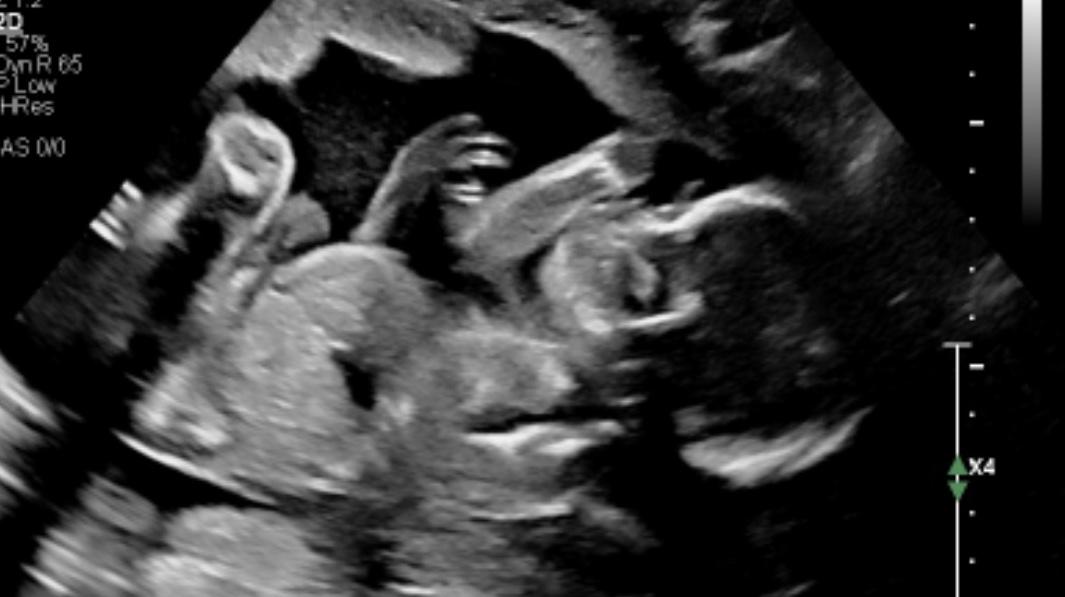

Juliette’s Baby Registry

Arrival date June 2, 2025

Braydon and I are so thankful for all of you, the amazing friends and family who’s love and support are invaluable in our lives. We are beyond excited to welcome our baby boy into that same love <3